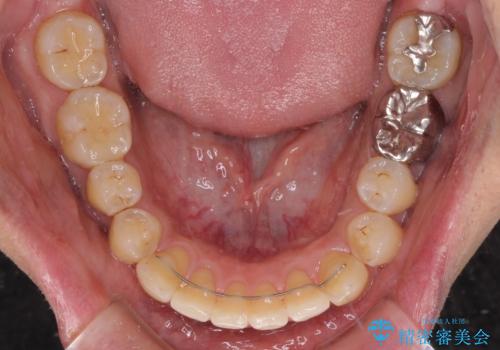

下顎前歯は後戻りを起こしやすいため、舌側を細いワイヤーで固定し、マウスピース型リテーナーで保定を行うこととしました。